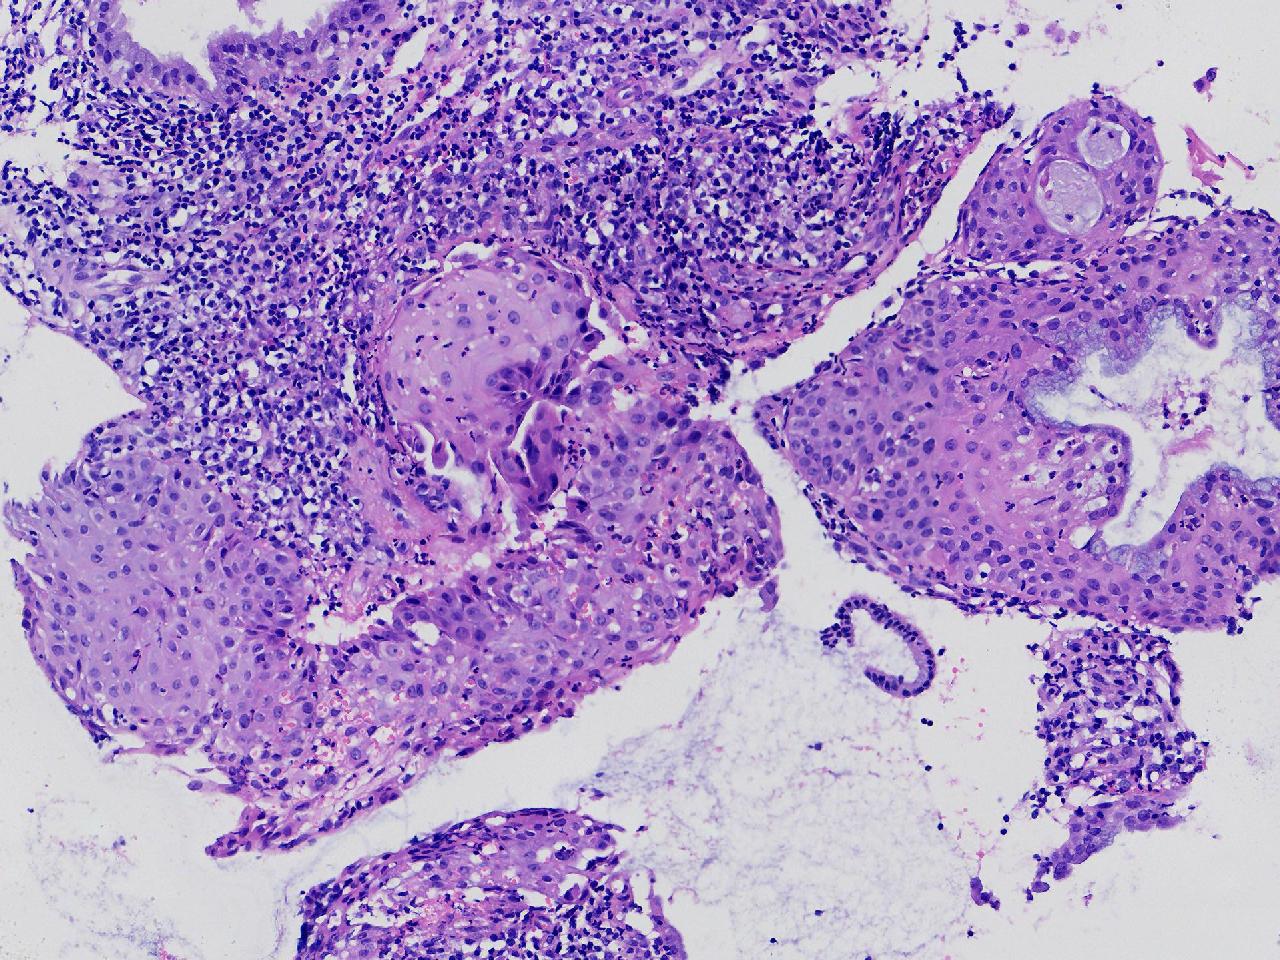

宫颈活检,有没有CIN?

女

36岁

宫颈病变

TCT示:ASC-US,HPV不详。

宫颈活检

图2

慢性宫颈炎伴腺上皮鳞化。

(宫颈活检组织) 慢性炎,储备细胞增生伴鳞化。